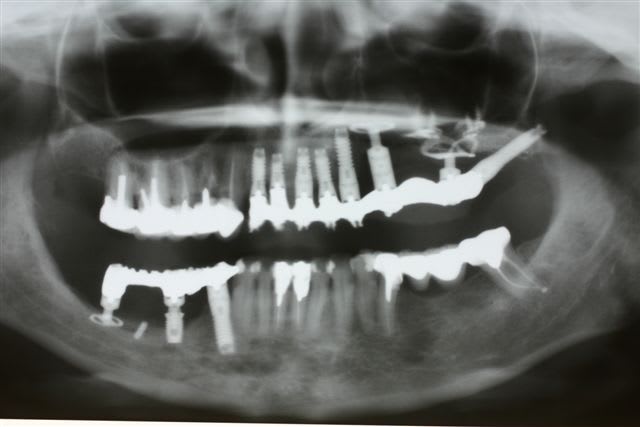

Perte d un greffon iliaque

Retraité en basale voici 6 ans avec succès